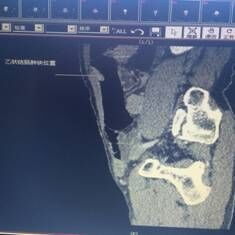

我院胃腸外科今年3月收治一名男性患者,以反復腹痛7月入院,CT提示胃竇部及乙狀結(jié)腸占位性病變(分別見圖1、2),行內(nèi)窺鏡活檢分別考慮胃腺癌以及乙狀結(jié)腸絨毛狀腺瘤,不排除惡變傾向。為改善患者生存率,減少創(chuàng)傷,手術(shù)團隊決定充分發(fā)揮腹腔鏡技術(shù)優(yōu)勢,采用腹腔鏡下一期同時切除胃、結(jié)腸病變,由于患者乙狀結(jié)腸病變惡性診斷不明確,根據(jù)腫瘤根治的原則,先處理乙狀結(jié)腸。手術(shù)當中依據(jù)冰凍切片,在腹腔鏡下首先完成乙狀結(jié)腸癌根治,后行腹腔鏡下遠端胃癌根治術(shù)。一次微創(chuàng)手術(shù),切除兩個腫瘤,免除了患者傳統(tǒng)剖腹手術(shù)及二次手術(shù)的創(chuàng)傷,縮短了住院時間,術(shù)后恢復快,降低了患者住院費用。

圖片1                               圖片2